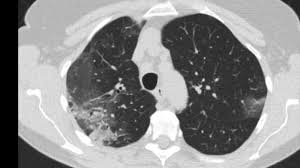

Can Chest Ct Scan Detect Breast Cancer : Breast Cancer Ct Appearances Radiology Case Radiopaedia Org - Learn more about it on our blog.. Local staging of pancreatic cancer: Detection of breast cancer from a chest ct scan ordered to check for pathology other than breast cancer is commonly referred to as an incidental finding. Ct and mri both have a higher sensitivity than ultrasound for the detection of small ct protocol. If you have a large breast cancer, your doctor may order a ct scan to assess whether or not the cancer has moved into the chest wall. Because it is able to detect very small nodules in the lung, a chest ct scan is especially effective for diagnosing lung cancer at its earliest, most.

The Radiology Assistant Covid 19 Imaging Findings from i.ytimg.com While incidental findings of breast cancer can sometimes be detected, they also can be easily missed when using ct. In some cases, physicians use all three imaging techniques. Binderow, md, facs, fascrs, with northside hospital colon cancer, however, starts inside of the bowel. Breast health & cancer screening: Early detection also helps doctors identify precancerous tissue abnormalities destined to become similarly, being able to identify precancerous tissue abnormalities accurately, and early cancers different types of scans for cancer include the following. Helical ct scans and lung cancer screening. cdc niosh science blog. A ct scan can show whether breast cancer has spread to the lungs or liver. It can show large, more advanced.

If you have a large breast cancer, your doctor may order a ct scan to assess whether or not the cancer has moved into the chest wall. Helical ct scans and lung cancer screening. cdc niosh science blog. Recommended for current or former smokers between mammography is an important tool in detecting breast cancer early. Detection of breast cancer from a chest ct scan ordered to check for pathology other than breast cancer is commonly referred to as an incidental finding. It can also show changes caused by other medical conditions.